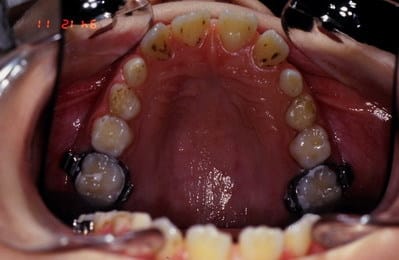

voici le 1er cas

Biproalveolie

1 a7nson - Eugenol

2 aijzeq - Eugenol

3 kwoluy - Eugenol

4 vduups - Eugenol

Cas n 1 suite

QH + Reeducation + Ecran buccal c'est tout